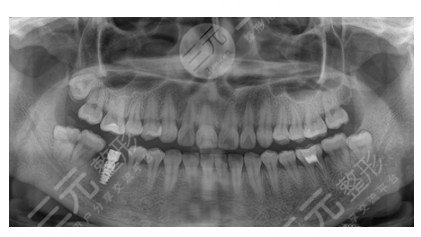

深圳友睦齿科种植牙案例

缝线结很紧,比拔牙多一根线。缝纫之后,手术终于结束了!我又做了一次电脑断层扫描,术后不用挂盐水。然后,当费用结时,花费比预期的要少。从深圳友睦齿科回家后,冰敷一直留着脸的脸颊,两三个冰袋交替使用。晚饭后,煮了瘦肉粥。这时候吞咽没有问题,因为有隐隐的疼痛,饭后吃药的时候也吃了止痛药。第二天醒来,觉得脸颊浮肿。

不疼。直到一周左右才几乎完全消肿。还有一件事,因为种植牙,口腔的消毒,在一周内换了一层皮肤,就像蜕皮一样。嘴巴的皮肤变成深棕色,然后变干并脱落。消毒强度真的很厉害。期间,我全用另一边的牙齿吃了,不敢过多刷牙,怕弄伤。我只坚持吃了一天粥。可以说,在深圳友睦齿科种植牙,之后的第1天就开始在晚餐上吃米饭,因为我是那种吃不下东西却想吃得更多的人。一周后,我开始放飞,吃着干米饭和各种美味的炒菜,然后在拆线前喝着奶茶,吃着烤肉。